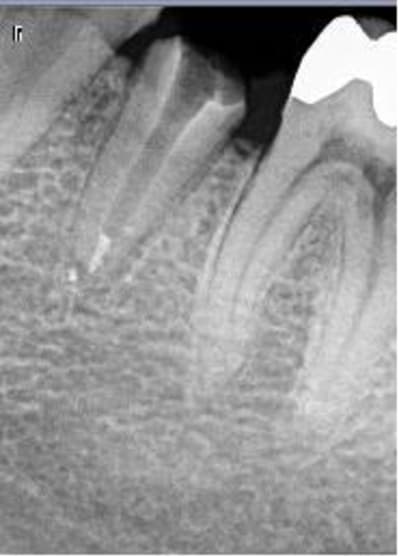

Patient de 35 ans, a fait la CCM sur 35 il y a Deux mois.

Arrive car douleur insupportable à la mastication.

A peine j'appuie légèrement, il saute au plafond.

Je dépose la couronne et le (volumineux !!) inlay core.

Toujours douleur à la pression quand j'appuie sur la racine.

Je ne vois que deux explications :

- Desmodontite par trauma occlusal (mais pas de poche !) ou surocclusion quelquonque (mais l'occlusion semble bien apres controle avec papier d'occlusion)

- Félure ou fracture ( vous voyez qqchose de suspect à la radio ?) mais la encore pas de poche...j'ai essayé la trasillumination je n'ai rien vu mais en meme temps vu l'effet de coin provoqué par l'inlay core présent.c'est possible quand meme..

Une autre radio, après dépose...

A l'apex vous ne voyez pas comme l'apex avec fracture horizontal ? en meme temps je l'ai trop regardé cette radio, elle m'aveugle !